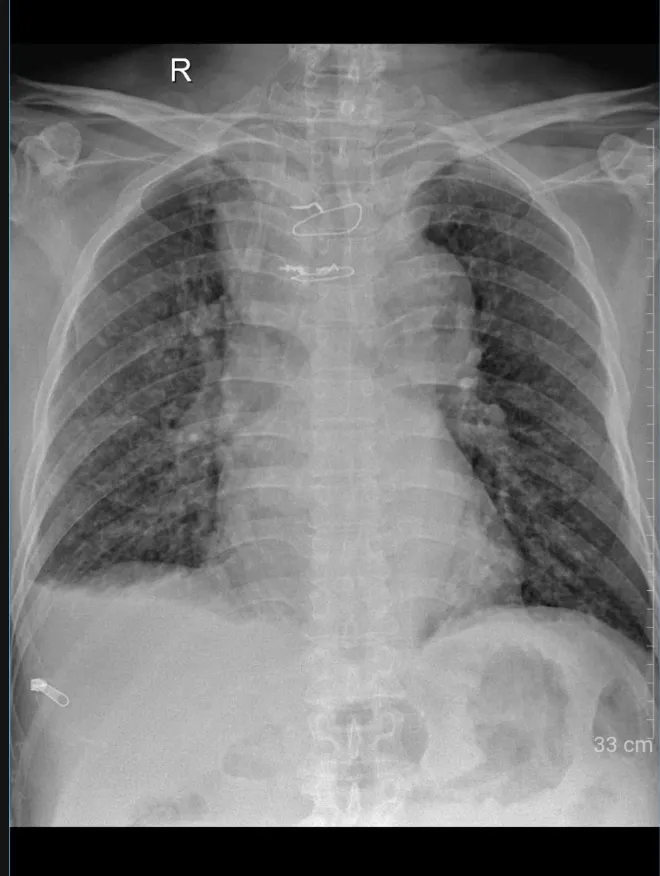

Phổi của người bệnh thông thoáng hơn sau phẫu thuật (Ảnhr: BVCC)

Sau phẫu thuật, người bệnh được chuyển về theo dõi tại khoa Ngoại lồng ngực mà không cần điều trị thêm tại khoa Hồi sức tích cực. Và chỉ vài ngày sau đó, người bệnh đã có thể hít thở sâu một cách nhẹ nhàng, ăn uống và sinh hoạt gần bình thường.